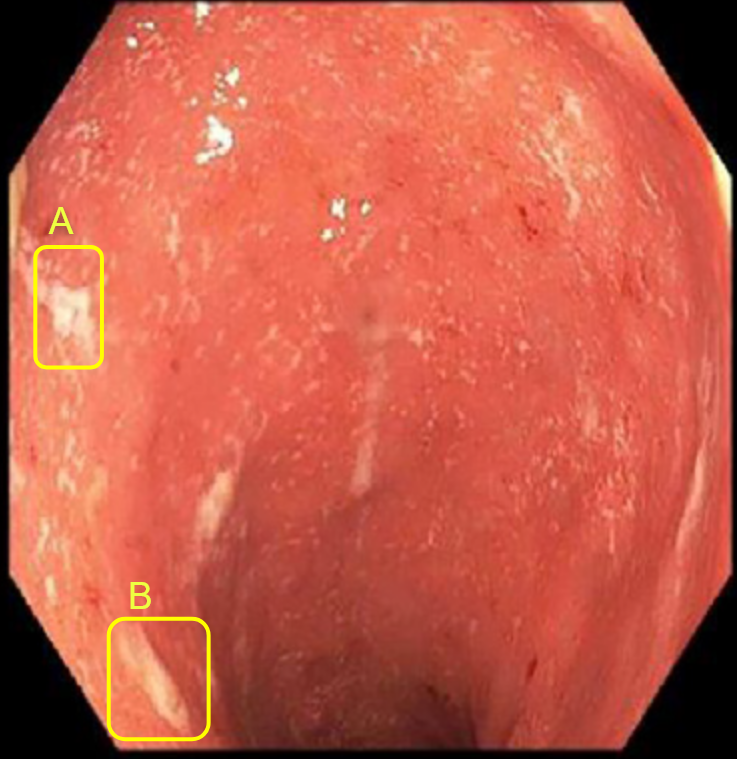

Now let’s move to biology which is the science of living organisms extending from the molecular level to the mesoscopic ecosystems. In this paper, we focus on the modelling of the inflammatory process hitting the bowel. Crohn’s disease and ulcerative colitis are both inflammatory bowel diseases but they are different indeed [15, 16]. Ulcerative colitis (UC) is a chronic inflammatory bowel disease resulting from an overreaction of the natural defenses of the digestive immune system, with an estimated prevalence of 1 in 1500 people with an annual incidence of 6 to 8 new cases per 100,000 inhabitants in Australia [17], Western Europe and the United States. In Tunisia, the incidence is estimated at 2.11 per 100,000 inhabitants per year [18, 19]. UC is not a rare disease in tunisian adults, but in children. It is characterized by smooth ulceration of the inner lining of the colon. The inflammation begins in the lower region of the colon, just above the anus, and progresses upward at varying distances. One of the most important indicators of the severity of this disease is the spatial distribution of the intestinal lesions associated with an introduced gastro-enterologist’s severity score. While individuals with moderate to high severity scores have a concentration of lesions around the rectum, those with low severity scores frequently have a homogeneous spatial distribution of colonic lesions. UC appears in lesions such as bleeding rectal and colon ulcers. It is a currently incurable disease characterized by varying intensities of inflammatory relapse with interspersed remission periods. This puts the patient at higher risk of colon cancer than the general population thus the potential removal of the organ (colectomy). Currently available treatments aim to control pain, reduce the frequency and duration of relapses, and thereby relieve symptoms. Crohn’s disease is a type of painful inflammatory bowel disease (IBD) that is not well understood. In Tunisia, this serious disease affects both children over 10 and adults [18]. It consists of the appearance of several asymmetrical segments of deep lesions separated by intact areas. In the worst cases, these areas can turn into fissures or even holes in the wall of the intestine. Unlike other IBDs, it affects any part of the gastrointestinal tract, from top (the mouth) to bottom (the anus), in contiguous or isolated parts. The inflammation can affect the inner lining and even go beyond the entire thickness of the intestinal wall; It is manifested by a blood vessels dilation and tissues fluid loss. It is usually present in the lower part of the small intestine that connects to the colon. The inflamed portion of the intestine affects the deep panniculus and is not adjacent to it, but rather is distributed throughout the gastrointestinal tract, with an erratic inflammation pattern. The diagnosis of this disease requires advanced technological tools which present difficulties in the collection of data to predict the spread. For that, the mathematical modeling has been increasingly utilized as a tool to understand the complex and dynamic processes involved in both diseases as shown in [5, 20].

In the evaluation and management of both Crohn’s disease and ulcerative colitis, doctors typically use a combination of biological, clinical, and spatial indicators to assess a patient’s condition, predict its progression, and determine the most appropriate treatment. Clinical indicators may include a physician’s examination and questioning of the patient, as well as video examination of the colon through colonoscopy. Biopsy samples taken during colonoscopy can also provide valuable histological images. In addition, biological or chemical indicators such as the measurement of calprotectin levels in stool (as an indicator of inflammation) and analysis of the intestinal microbiota through DNA and RNA analysis can provide important insights into the disease. Additionally, analysis of RNA expression in the intestine can also be used as an indicator.

Gastro-enterologists and surgeons are hindered from having spatial information on anatomical sites since these indicators are not spatial, and the provided information is never localized in a specific position. The diagnosis of these diseases is based on the analysis of colonoscopy videos. Thus, physicians assess the severity of the disease according to the presence of inflammation, bleeding or ulcers on the intestinal wall which requires an advanced level of expertise. In the same way, the extent of the lesions is currently ignored in medical practice, for lack of a validated method for analyzing this information. This same remark applies to other indicators like numerical score of severity [21], the speed of inflammation propagation, the choice of treatment [22]. Gastroenterologists recognize the significance of spatial information in the development of complications such as esophageal and colon cancer in patients with Crohn’s disease and ulcerative colitis. However, current guidelines fail to fully consider the quantity and distribution of lesions, often focusing solely on the most severe lesion identified. This is due to the scarcity of software tools and scientific literature. Additionally, the intricate feedback loops and technical challenges in collecting high-quality data for the calibration of numerical and mathematical models (see figure 2) further highlights the need for innovative methods. This necessity is the driving force behind our current study, which aims to address the limitations in current approaches and provide a more comprehensive understanding of the disease.

Endoscopic video analysis [24] plays a crucial role in evaluating the severity of ulcerative colitis and monitoring the progression of the disease. Colonoscopy is widely used as the reference examination to assess the intensity of the disease and the extent of intestinal lesions. During this routine procedure, a gastroenterologist inserts a camera-equipped endoscope into the colon to visualize the inner lining and take biopsies if necessary. It should be noted that this technique has a very strong impact on the quality of life of the patients.

Both colonoscopy and WCE allow for the detection of important lesions in the videos, such as: Loss of visibility of the vascular framework, which is indicated by the disappearance of blood vessels and the formation of fibrous tissue that impedes nutrient absorption and inflammation and bleeding, which appear as red areas on the intestinal wall and ulcers and indentations in the wall that appear white or gray. The precise collection and examination of the endoscopic video data is essential not only for identifying the disease presence and advancement, but also for categorizing the different types of IBDs and classifying the subtypes within the same disease.